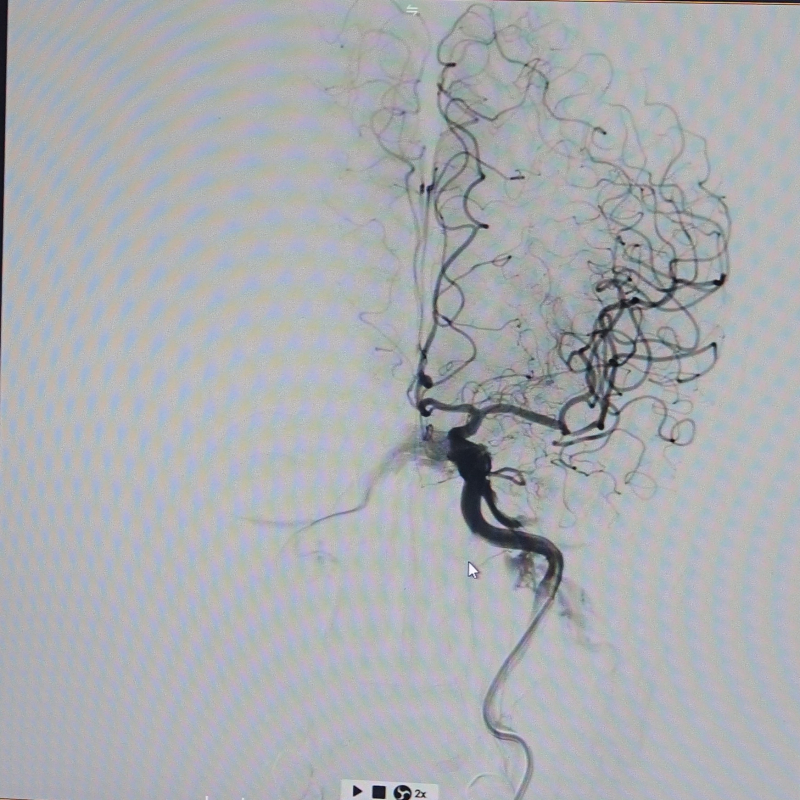

Hình ảnh: Sau can thiệp

Sau khi được các bác sĩ can thiệp và điều trị tích cực, tình trạng bệnh nhân cải thiện rõ rệt. Sau 1 tuần điều trị, bệnh nhân tỉnh táo, chức năng vận động phục hồi đáng kể. Nếu như lúc nhập viện, cơ lực tay trái chỉ đạt 1/5, chân trái 2/5, thì hiện nay tay trái đã phục hồi khoảng 4/5, chân trái đạt 5/5. Bệnh nhân đã có thể tự đi lại và sinh hoạt gần như bình thường.